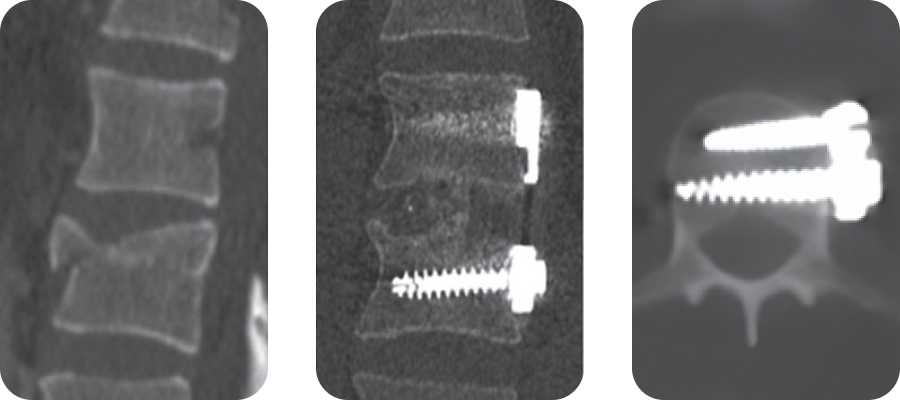

Клинический пример 2

- Неполный взрывной перелом тела Th12-позвонка (А 3.1).

- Тело позвонка Th12 замещено имплантом ObeliskPro и выполнена фиксация пластиной GoldenGate®